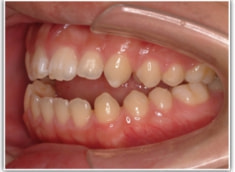

開咬(かいこう:オープンバイト)ケース

治療法:表の矯正(T21ブラケット)

(インプラントアンカーや外科矯正は行わず、エラスティックと機能訓練のみ)

治療前